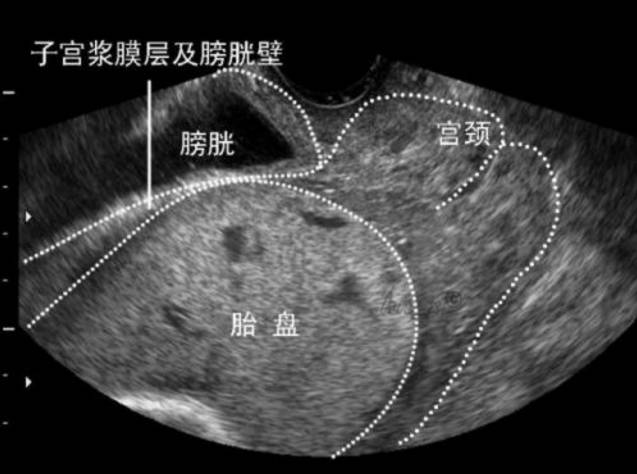

胎盘植入诊断常较困难,部分可经产前B超及核磁共振检查诊断,但仍有大量病例于分娩时胎盘未能剥离及产时产后大出血才诊断出来。虽然分娩时胎盘植入可通过血管阻断术、子宫压迫缝合术和宫腔填塞等治疗方法预防及治疗产后出血,但胎盘强行剥离后仍有较高的产后出血几率,需行子宫切除术。

MRI下胎盘植入HIFU治疗前后对比图